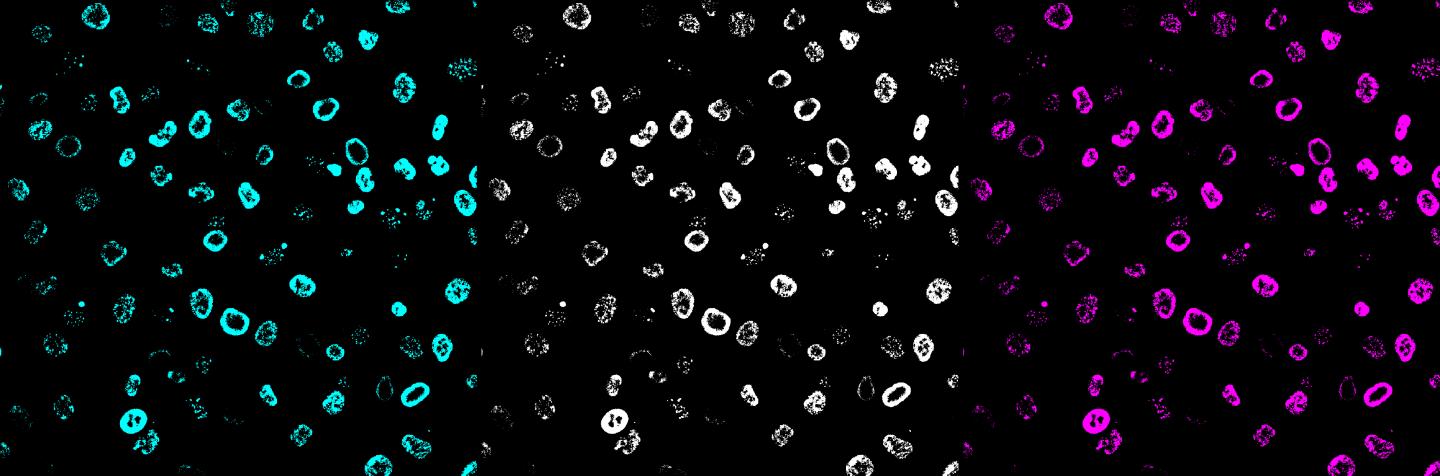

image: RINGs of DNA damage in human cells caused by the typhoid toxin underlying typhoid fever.

Using fluorescent microscopes to study how the toxin damaged the DNA at the molecular level, they discovered it induces a peculiar form of DNA damage; the toxin takes over DNA repair machines and accelerates cellular ageing, rendering them more susceptible to infection. In time, secretions from the infected cells can also cause aging in neighbouring cells, leading to faster aging at a cellular level.

To cause typhoid, the bacterial pathogen Salmonella typhi releases the typhoid toxin, which damages cellular DNA. Our DNA is constantly under threat by environmental factors such as smoking and UV light, but cells usually have robust DNA repair machines to combat these threats. In the case of the typhoid toxin attacking our cells, it is this repair machine function that gets hijacked. Dr Angela Ibler who made the discovery dubbed the DNA damage response RING - Response induced by a Genotoxin - in reference to the single-strand breaks in the double helix of human cell DNA that accumulate in a signature ring-like pattern.